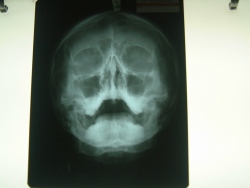

Plain X-Rays & Digital X-Rays Films

What are X-rays?

X-rays are electro-magnetic radiation,

which are produced by special machines called X-ray machines. These cannot be

seen, felt or heard.

How do X-rays work?

Different parts of the body behave differently with X-rays. Structures

such as bone absorb X-rays, whereas air in the lungs lets all X-rays

pass through. Thus, when X-rays pass through the body, when they come

out, they have different strengths, depending on what parts of the body

they have passed through. When these X-rays hit a film (like a

photographic film), that film gets exposed depending upon this

variation. Like a photographic film, this special film also needs to be

developed, before we can see the final picture.

Where are X-rays useful?

X-rays have been used to look at all parts of the body.

Specifically, they are required for the chest, all bones and joints and

for the abdomen.